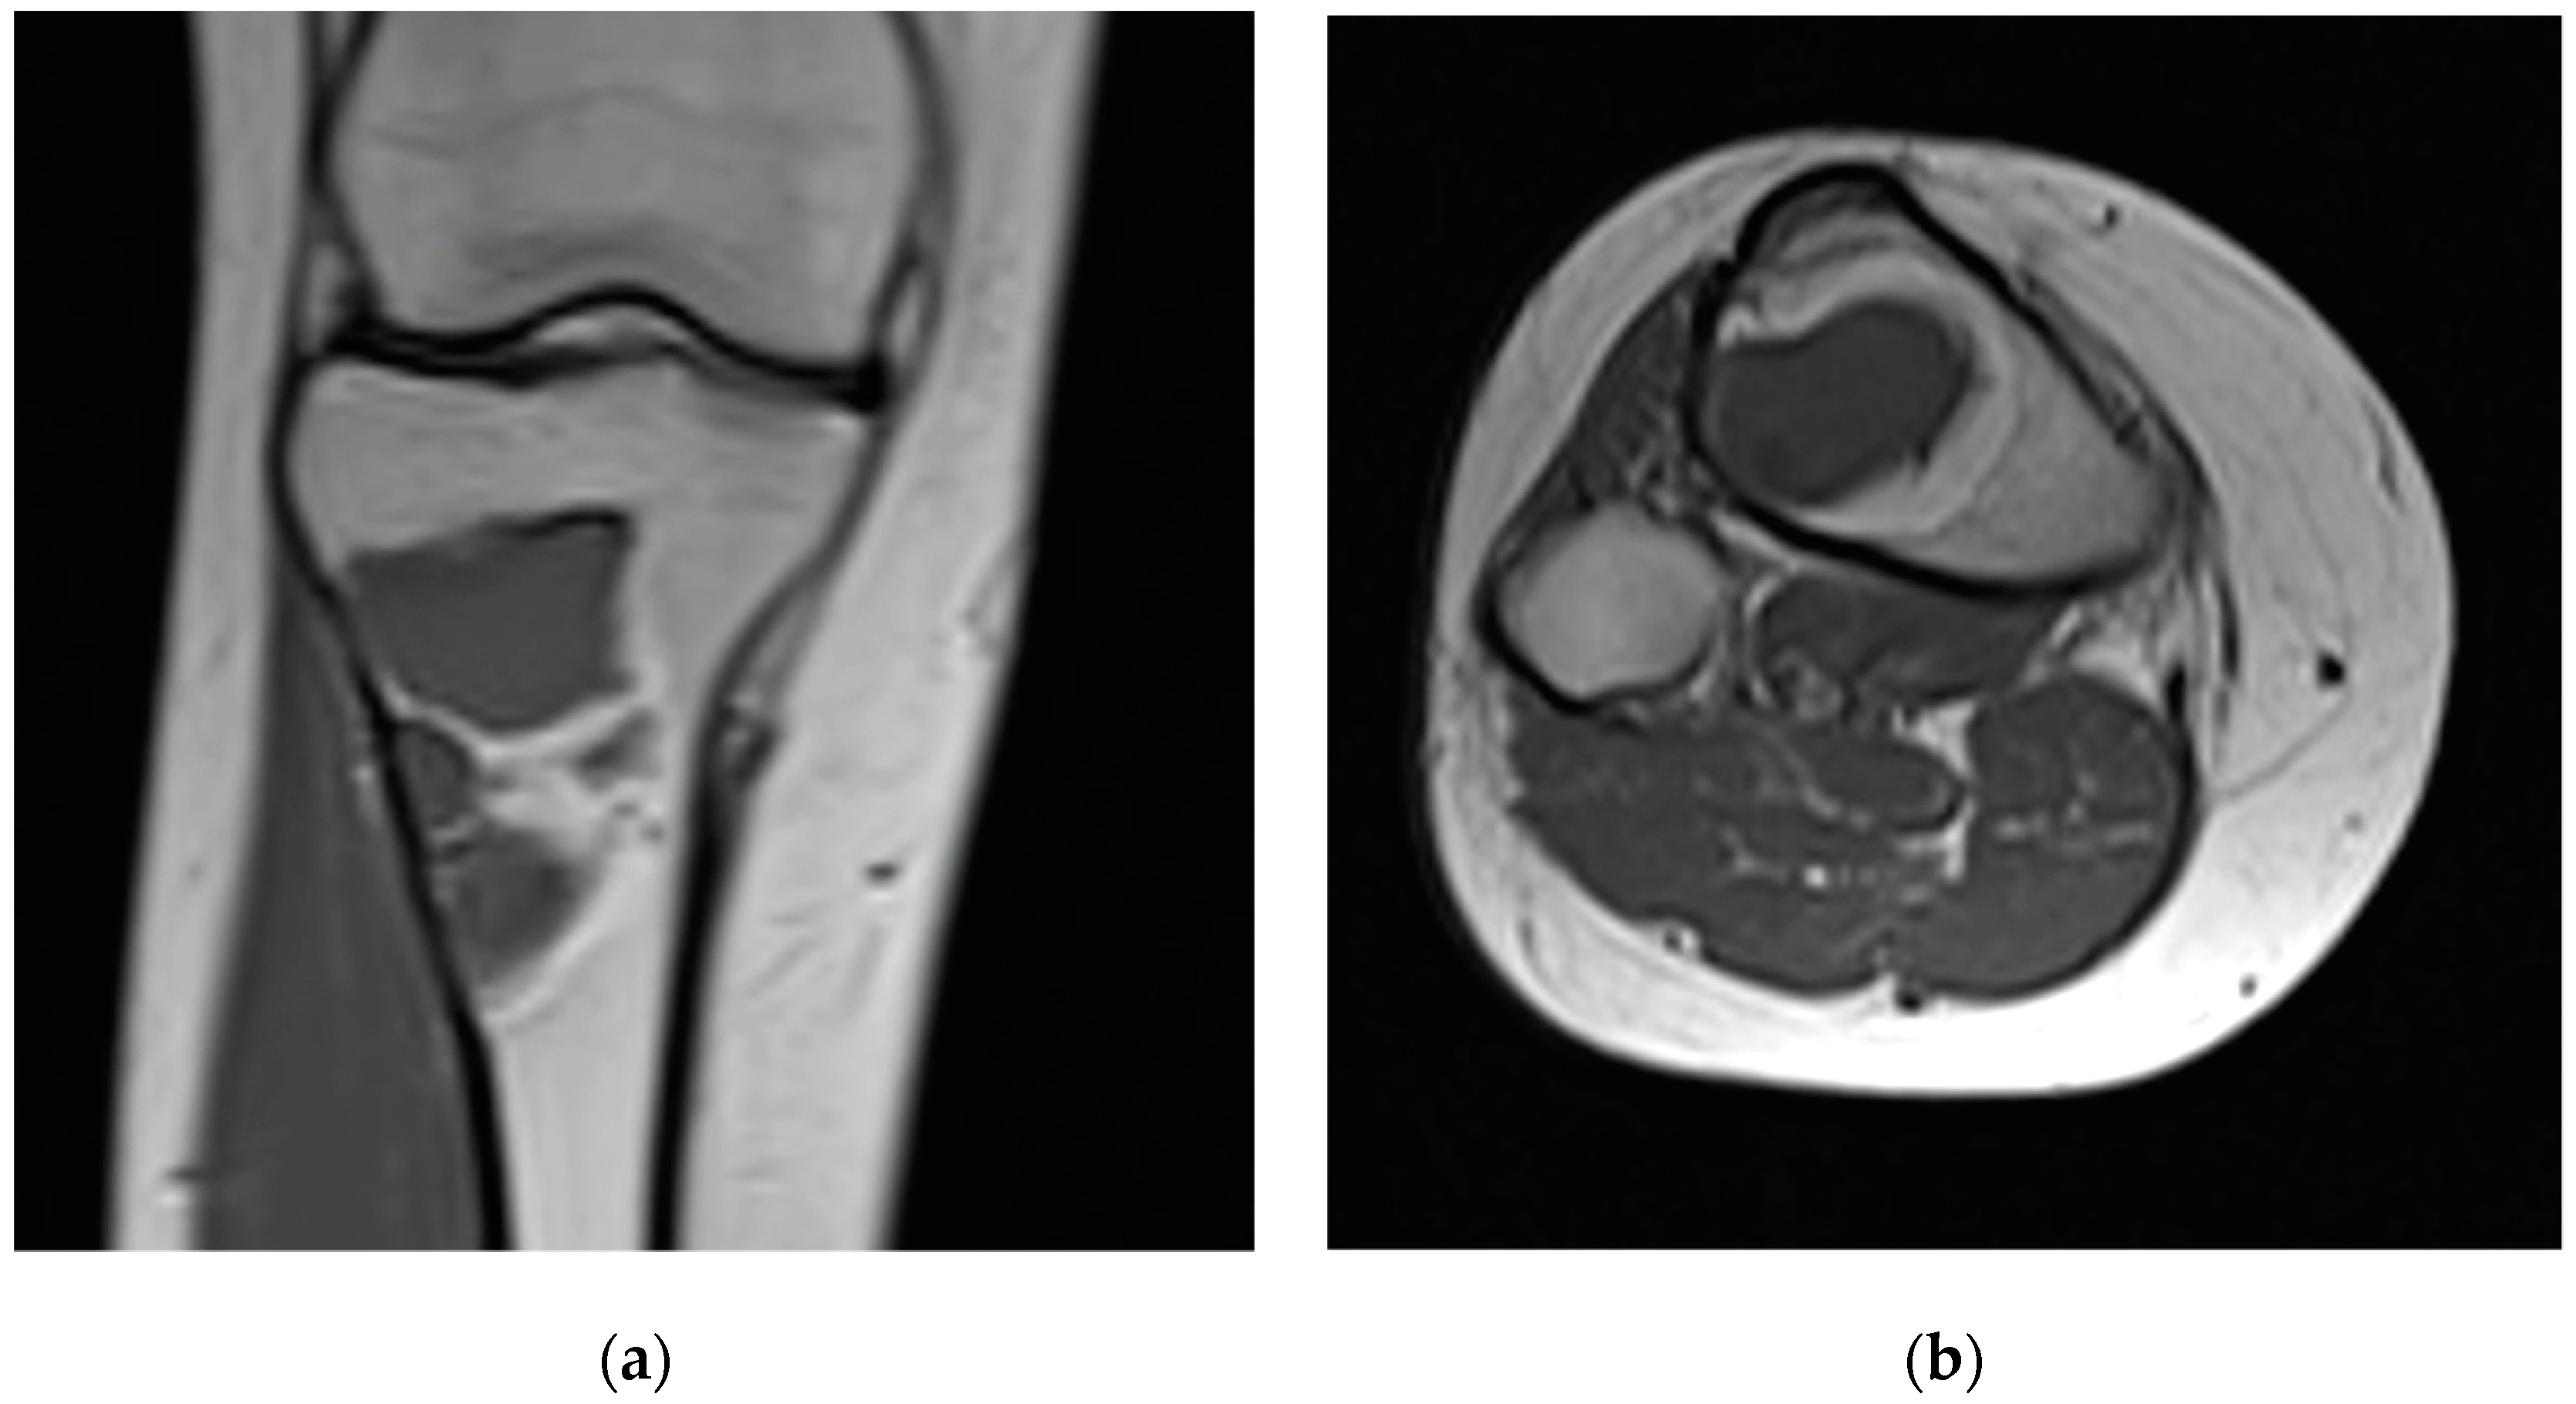

| 3 | 17 F | 1 | Right proximal tibia | 58 | Fibrous dysplasia | 22 |

| 9 | 27 F | 1 | Left tibial diaphysis | 41 | Fibrous dysplasia | 23 |